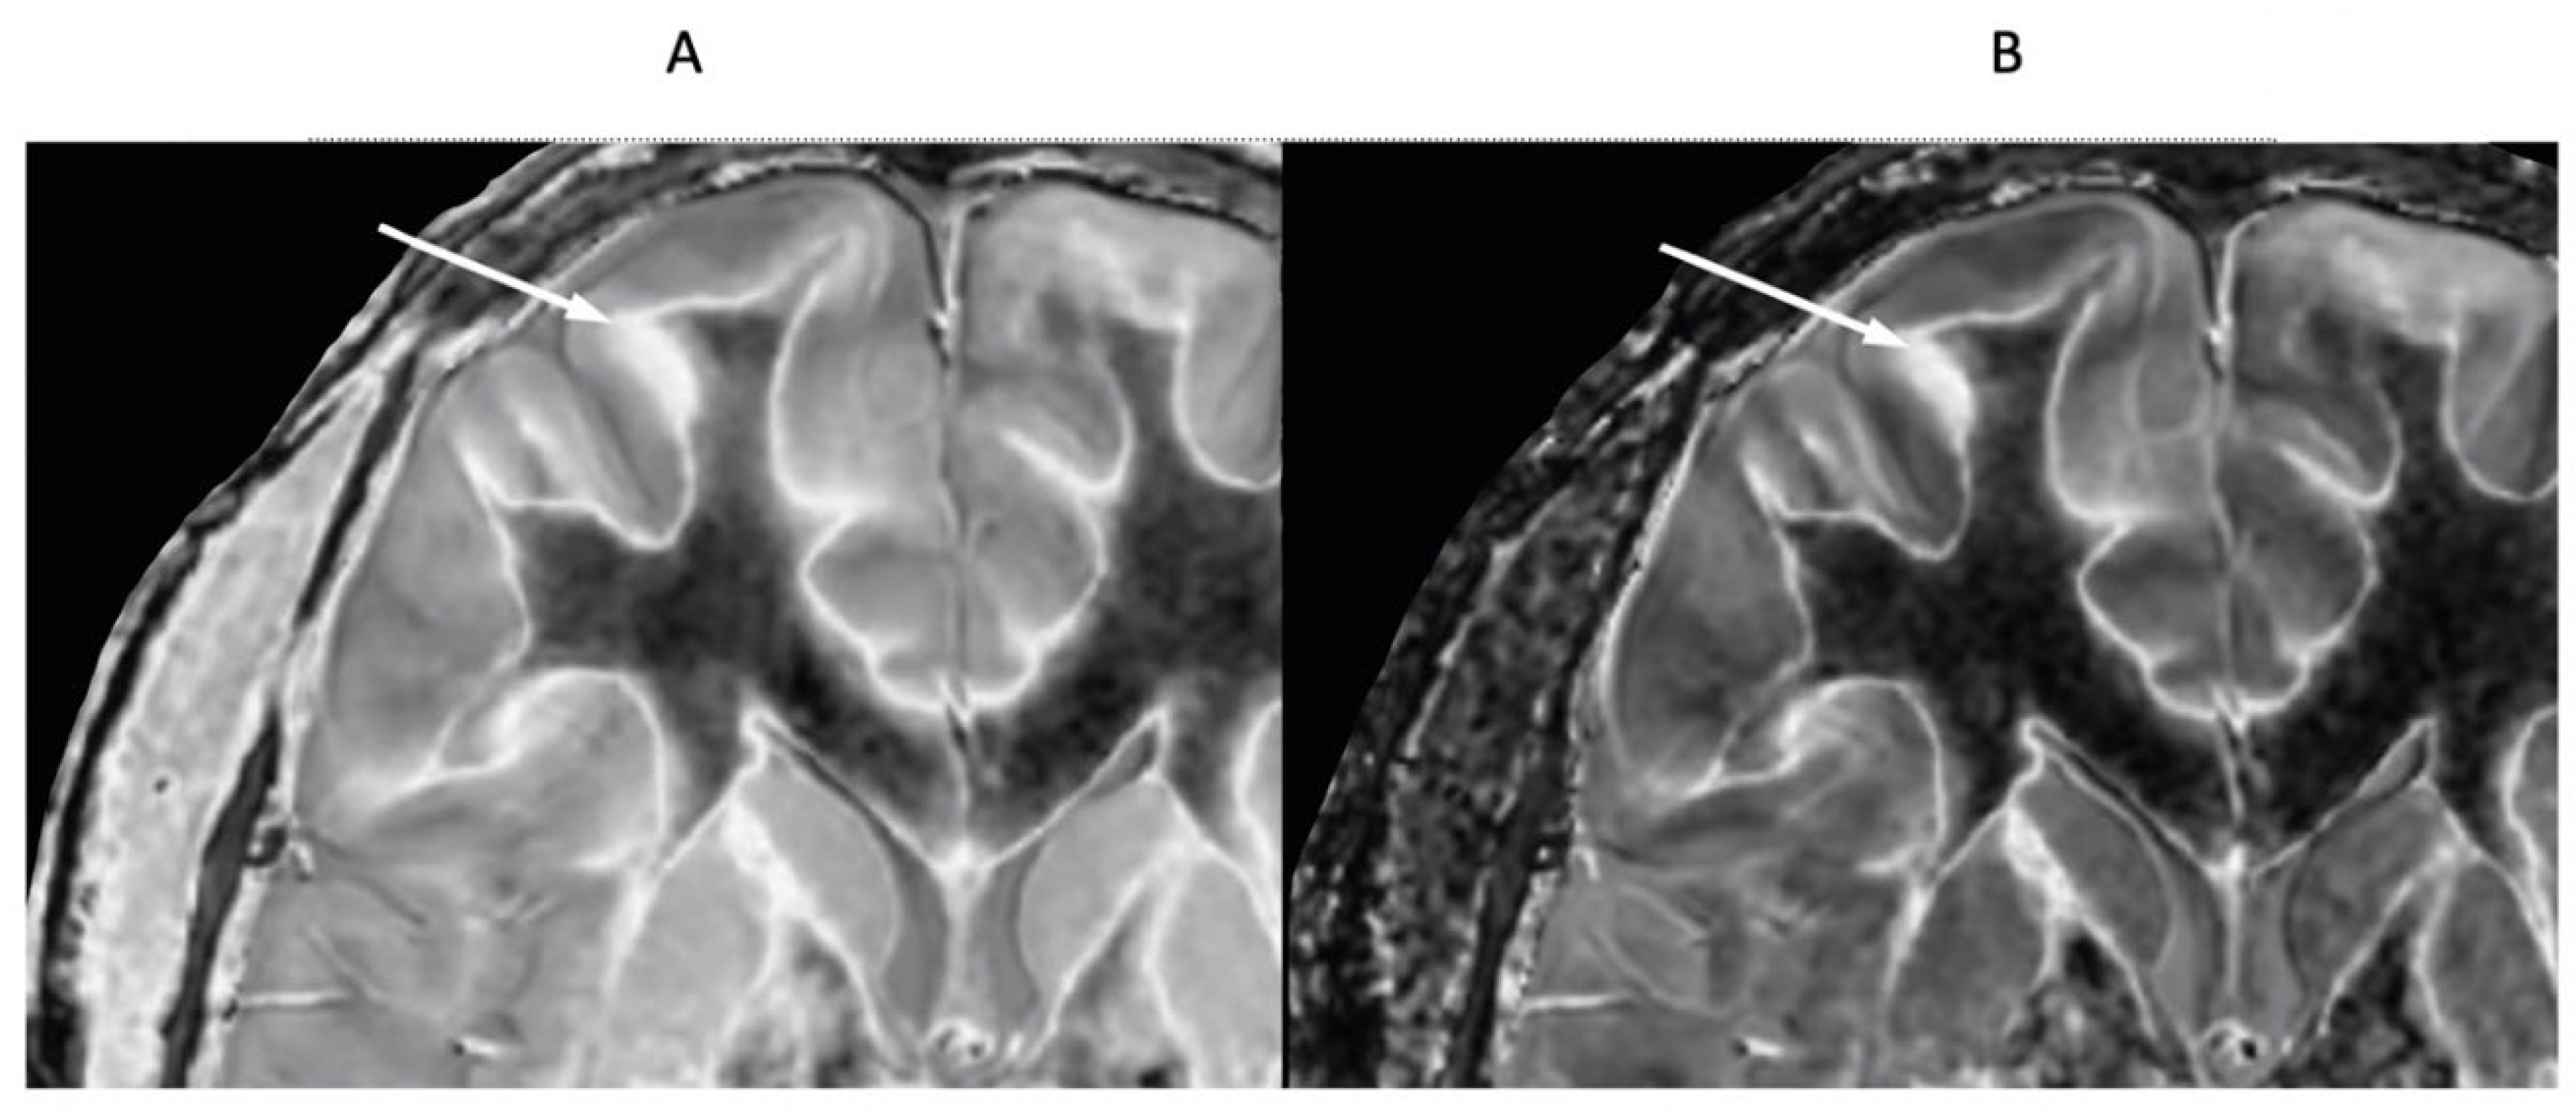

18-year-old patient with mTBI 21h (A) and 64h (B) post injury imaged with the same narrow mD dSIR sequence. In (A) the patient shows a whiteout sign (grade 4 out of 5) with high signal in most of the white matter in the cerebral hemispheres except for the anterior and posterior central corpus callosum. The posterior limb of the internal capsule is high signal. The thalami show low internal contrast from medial to lateral (arrows on lateral margins of the thalami). There is also low external contrast between the lateral margins of the thalami and the adjacent posterior limbs of the internal capsule. On the follow up examination at 64h (B) the whiteout sign has resolved and there is low signal in the white matter including the posterior limbs of the internal capsule (except for the corticospinal tracts). The thalami now show high internal contrast from medial to lateral (arrows on lateral margins of the thalamus) which is the normal appearance at this age. There is now also very high external contrast between the lateral margin of the thalamus and the adjacent posterior limb of the internal capsule. Image (A) shows the grayout sign which is a reduction in the high contrast between the medial and lateral gray matter of the thalamus. The high contrast is restored in (B). No abnormality was seen on the corresponding T2-FLAIR images obtained at both time points.

Figure 12.